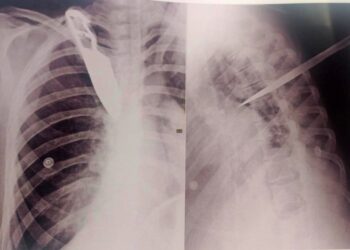

Mulher é esfaqueada por detento em ‘saidinha’ de fim de ano e imagem do raio-x mostra faca cravada nela

GÁLIA (SP) – A imagem de um raio-x com uma faca cravada nas costas chocou as pessoas que souberam o ...